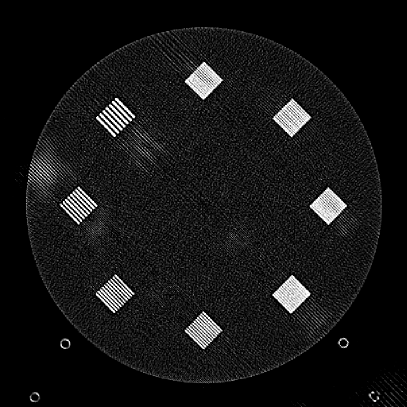

Refer to caption

(a)

(b)

Figure 9: (a) The ACR phantom module 1 with 4 different inserts for CT number fidelity testing. In addition, two ramps of wires are visible near the phantom center. The image display window center is 150 HU and window width is 700 HU. (b) The phantom module 3 with a uniform water-equivalent radiodensity of 0 HU. The display window center is 0 HU and window width is 400 HU.

To evaluate image quality, we first tested the performance of JENG on a standard CT phantom, CT ACR 464 phantom 35. Then we tested JENG on 5 clinical thoracic datasets and 3 abdominal datasets. The ACR 464 phantom contains four modules in total, with each module 40 mm in depth and 200 mm in diameter. The first module has 4 different inserts to test CT number fidelity. In addition, the module contains a series of wires for cross-plane resolution evaluation, shown as white horizontal bars near the center in Fig. 9(a), and are visible in 0.5 mm z-axis increments. The second module tests low contrast resolution, but is not used in this paper. The third module, shown in Fig. 9(b), is a uniform cylinder of water-equivalent material of 0 Hounsfield units (HU), and we used this module to quantitatively measure image noise profile and in-plane resolution. The fourth module consists of resolution bars of various spatial frequencies for analysis on high contrast resolution. To scan the phantom, the scanner setup used dual sources with 2 focal spots at each source. In addition, the projections were acquired using the same protocol for clinical thoracic scans with 100 KV, a nominal tube current of 718 mA and a high helical pitch of 2.8. For all experiments, we compared JENG against the state-of-the-art Siemens ADMIRE, reconstructed with a BL-64 soft tissue sharp kernel, and we define ADMIRE as the clinical standard hybrid IR method for the rest of the paper.